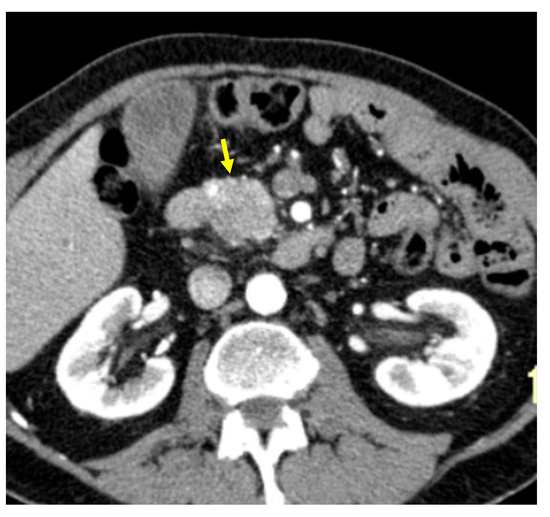

Tumor margins showed a significant difference in the two groups, appearing well-defined in only 6 (6.98%) metastatic patients and ill-defined in the remaining 80 (93.02%); in the non-metastatic group, the margins appeared well-defined in 132 (65.35%) and ill-defined in 70 (34.65%) tumors (Figure 2, Figure 3, Figure 4 and Figure 5).

Visual lesion assessment in the portal-venous phase showed a significant statistical difference in the two groups, appearing hypodense, respectively, in 80 (93.02%) metastatic patients and 108 (53.46%) non-metastatic patients.

Figure 5. Pancreatic lesion with ill-defined margins (arrow) on CT examination in portal-venous contrast phase.